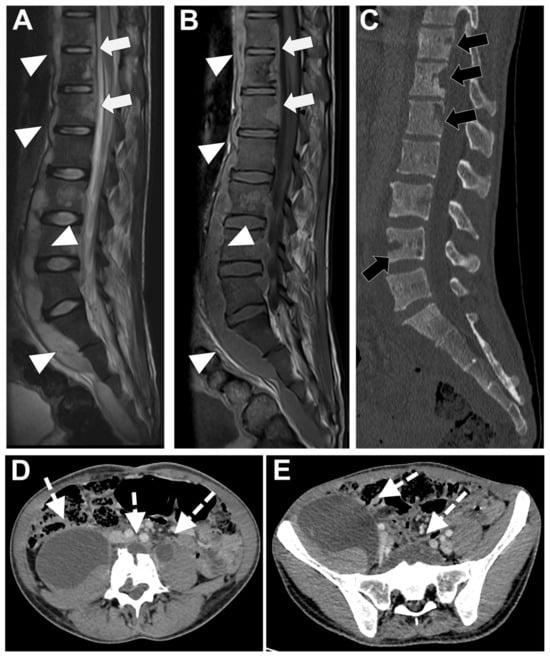

In Figure 6 an exemplificative case of TbS is presented.

Figure 6. Tubercular spondylodiscitis. A 24-year-old man of Sudanese origin presented with thoracic and lumbar pain evolving for several months. An MRI was performed with (A) T2-weighted imaging (WI) and (B) contrast-enhanced (CE) T1-WI, as well as a CT-scan in bone kernel (C) and abdominal kernel after contrast medium injection (D,E). It demonstrates preserved disk but extensive sub ligamentous collections spreading along the anterior side of the thoracic and lumbar vertebral bodies (white arrowhead), but also along the posterior vertebral collateral ligament (white arrows) with large anterior and posterior erosions (black arrows). Please note the extensive collections spreading in the presacral space and along bilateral iliopsoas muscles without surrounding inflammation (white dashed arrows).